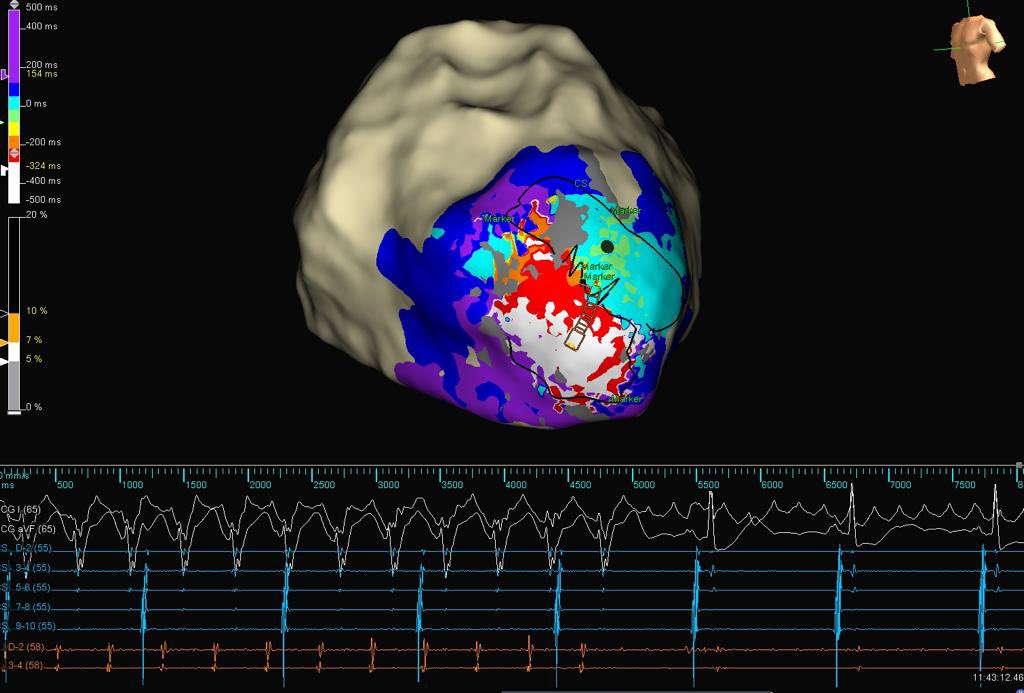

@Callme_DrNeil @ivroca @ozgursurgitMD @EPteam_IMAEH @MBassorkun @nailguven_dr Not completely sure based on the propagation. Would be nice to signals at the Marker Marker zone

@ivroca @ozgursurgitMD @EPteam_IMAEH @MBassorkun @nailguven_dr @JVGEP where do you think the missed 3d portion is?

Last surprise of 2022!! 48 year old patient with incessant VT unfortunately with apical thrombus formation.Lucky epicardial VT ablation…#EPeeps

@DrRoderickTung @DrKatrapati @Peteweissmd @su_wilber @MikeZawanehMD Critical isthmus at 11-12 with local EGM stepping out coinciding with TCL jump by 40msec. Suggests circuit has multiple layer components. 12-lead QRS Exit same for both TCL.

Happy Thanksgiving to all! This was a delicious diastolic buffet leading into the holiday with our new tridecapolar catheter in inferoapical scar. 🍗🍽️The intricacies and complexity of this dish are deep..#ablateVT